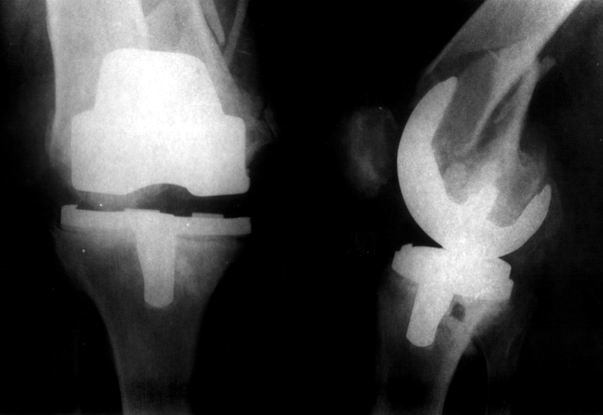

Видимо, самое "модное" на сегодня - малоинвазивный остеосинтез пластиной с угловой стабильностью. Распространенный вариант и закрытый интромедуллярный остеосинтез ретроградно. Хотя у нас было бы сделано антеградно - лешево и сердито, действительно малоинвазивно, в сустав не надо влезать. Нет риска прорезания порозной кости с миграцией в сустав, что возможно при ретроградном - гвоздь вводится через вырез в бедреннм компоненте, туда же может и вывалиться. А антеградный - упрется в протез. Как раз вчера заходил больной через полтора года после такой операции. Снимки в приложении.

на снимке признаки loosening и тибиального и феморального компонентов я думаю нужна ревизия если нет возможностей то артродез и конечно исключить инфекцию . успехов .

Мне представляется следующее: Если дистальный отдел бедра расколот и в сагиттальной и во фронтальной плоскостях, как видно на рентгенограммах, и при этом есть смещение отломков относительно друг друга и бедренного компонента эндоаротеза, разве от может оставаться стабильным? В случае отсутствия проблем с тибиальным компонентом, можно было бы надеяться только на остеосинтез и стабилизацию, но если предполагается ревизия в ближайшие месяцы/год, то не лучше ли за один раз решить несколько проблем?